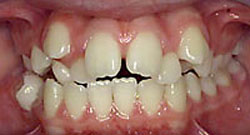

- *Răng mọc chen chúc:

- Răng mọc chen chúc là tình trạng các răng sắp xếp lộn xộn, không ngay ngắn trên cung hàm , răng mọc không đều, các răng khấp khểnh do thiếu chỗ (răng quá to hay xương hàm cung răng quá nhỏ không đủ chỗ để các răng sắp xếp).